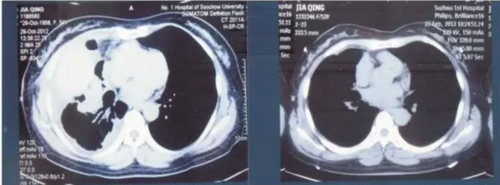

肺腺癌:贾青,女,55岁,2012年10月体检发现右上肺4cm肿块,CT示右上肺癌伴两肺散在性结节,病理确诊为肺腺癌EGFR突变型。至2012年12月病情进展并发胸水,因拒绝放、化疗,经应用参苓白术散、牛黄醒消丸及易瑞沙,临床症状消失。CT复查右上肺肿块消失,胸水亦消失。